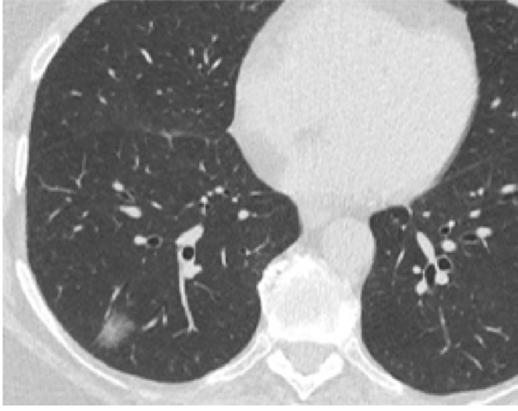

Mynd 6-1 Lítið lungnakrabbamein í hægra lunga (ör) sem fannst við skimun með tölvusneiðmyndum.

Með tilkomu tölvusneiðmyndatækni (TS) varð unnt að finna mun smærri hnúta í lungum en áður var mögulegt með hefðbundnum röntgenmyndum (mynd 6-1). Á síðustu áratugum hefur verið efnt til stórra framvirkra samstarfsverkefna, bæði í Bandaríkjunum og Evrópu. Fyrstu rannsóknir á skimun með TS voru gerðar í Japan og fyrsta alþjóðlega rannsóknin benti til þess að unnt væri að finna um